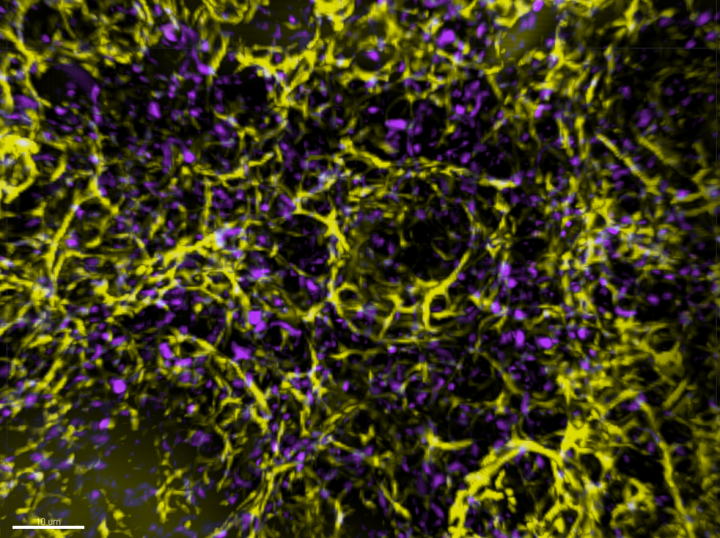

Published in Science Advances, the study performed high-resolution imaging and revealed that the neighbouring cells have a process that applies mechanical force to split the dying cells into smaller fragments before consuming them.

Photo caption: Optically cleared tissue sections of the thymus. Yellow – epithelial cells; Magenta – dying cells.